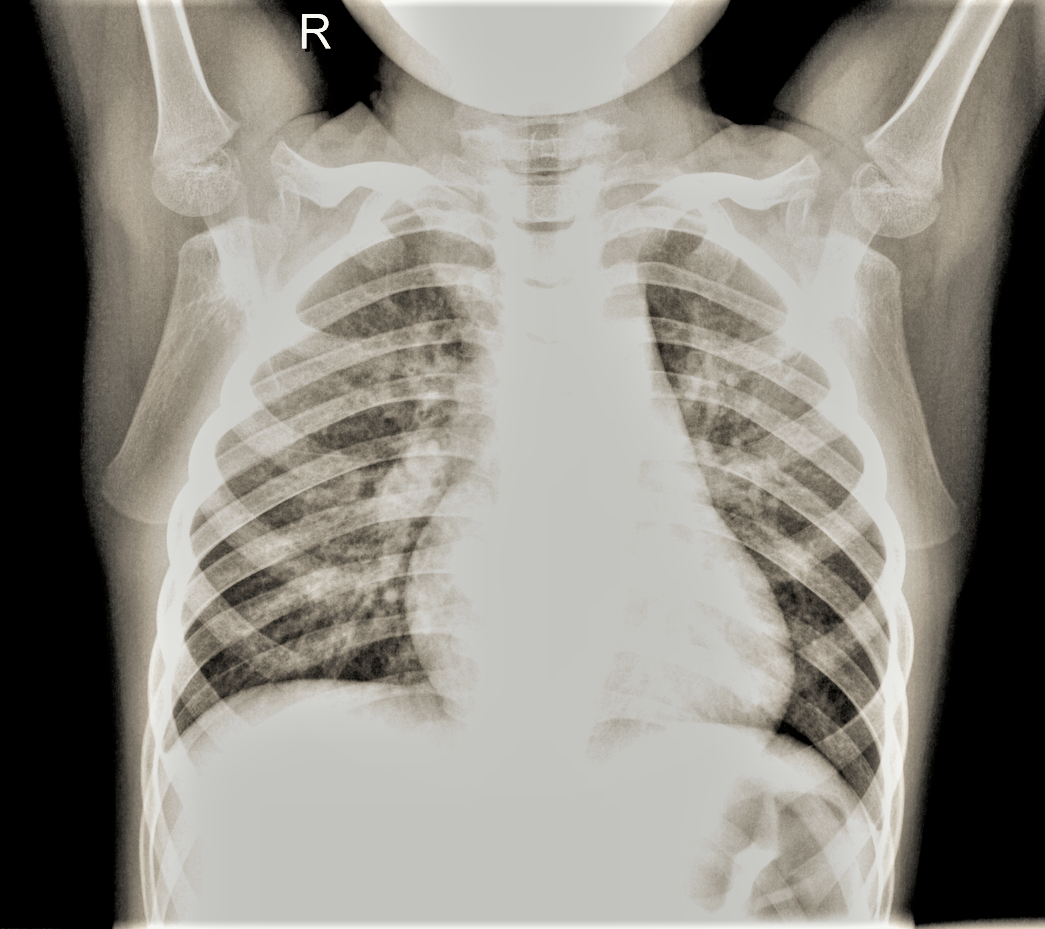

The finalized version of the image after our pre-processing pipeline can be found in fig 6. The image we created enables certain details to emerge so that the convolutional neural network can better detect any differences that indicate either an image is pneumonia or not.

Refer to caption

Figure 6: X-ray Image with combined pre-processing methods applied